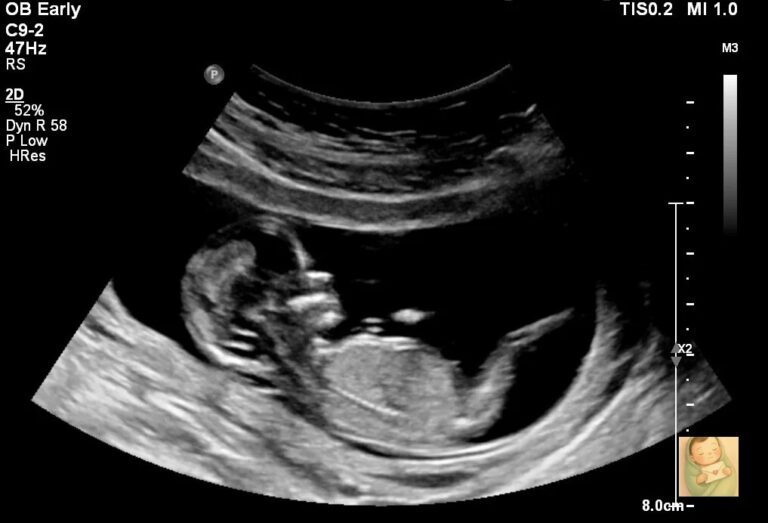

怀孕二十周做B超时,医生说胎盘有点低,盖住了宫颈口。因为是头胎,他说一般情况胎盘会自己长上去。

我被推进产房,医生检查宫口有没有开。还好,没开。我屏住呼吸等他们听你的心跳——终于听到了,咚咚咚的,特别有力,好像什么事都没发生一样。

如果不是住院,我反而会错过很多祝福。每天早晨,助产士都会推着胎心监护仪进来,听你的心跳。这成了我们娘俩每天的专属时光。每一天,我都在琢磨你在肚子里的动静——踢我的时候心跳会变快,我慢慢学会了摸出你的小屁股、小后背、小脑袋在哪儿。后来助产士来检查,我都能直接指出你胸口的位置。